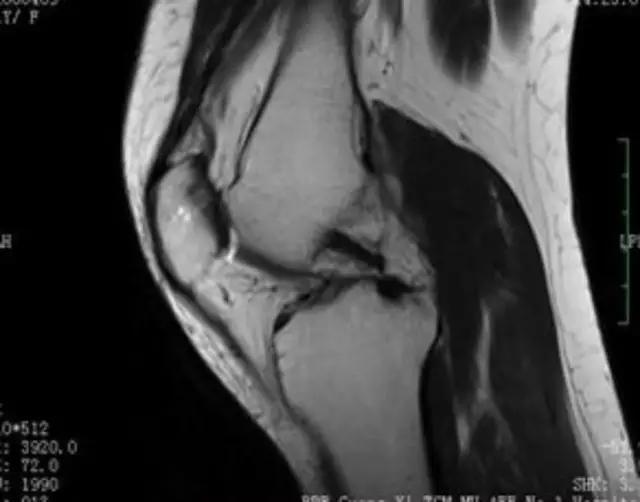

下图是同一个病人的MRI照片,MRI显示的内容更多,包括骨与软策划等,很多早期的、细微的病变都能清晰显示,其诊断报告对病人导致的影响也更大!

我们可能都不熟悉T1、T2,怎么办?当我们发现有问题后,利用照片上图像的对比,推测病变的可能也是一种诊断方法。病例:黄XX,女,39岁,左膝关节反复交锁1年。图1:肿物信号与骨信号一样图2:肿物信号与骨信号一样图3:肿物信号与骨信号不一样 肿物应该与骨相关,但不是骨性,推断:膝关节滑膜软骨瘤。手术后得到证实。